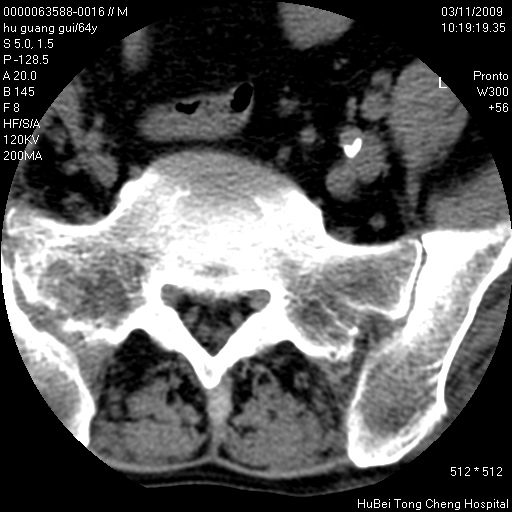

患者 男,64岁。腰痛十余天。(临床未提供其他病史)

临床诊断:腰痛原因待查(腰椎间盘突出症?)。

腰椎间盘ct轴位平扫(层厚5mm,层距4mm),图像如下:

腰椎退行性变,腰4—5椎间盘膨出。

右侧骶骨侧块骨侵蚀,骶髂关节骨性关节面破坏,并见软组织肿块,考虑骨转移瘤可能,进一步检查。

1.腰椎退行性变,腰4—5椎间盘膨出。

2.右侧骶骨侧块骨侵蚀,骶髂关节骨性关节面破坏,并见软组织肿块,考虑:脊索瘤,骨转移瘤可能,进一步检查。

1)腰椎退行性变,l4—5椎间盘膨出。2)骶骨右侧块骨转移瘤可能,3)水平骶椎。建议作一步检查。